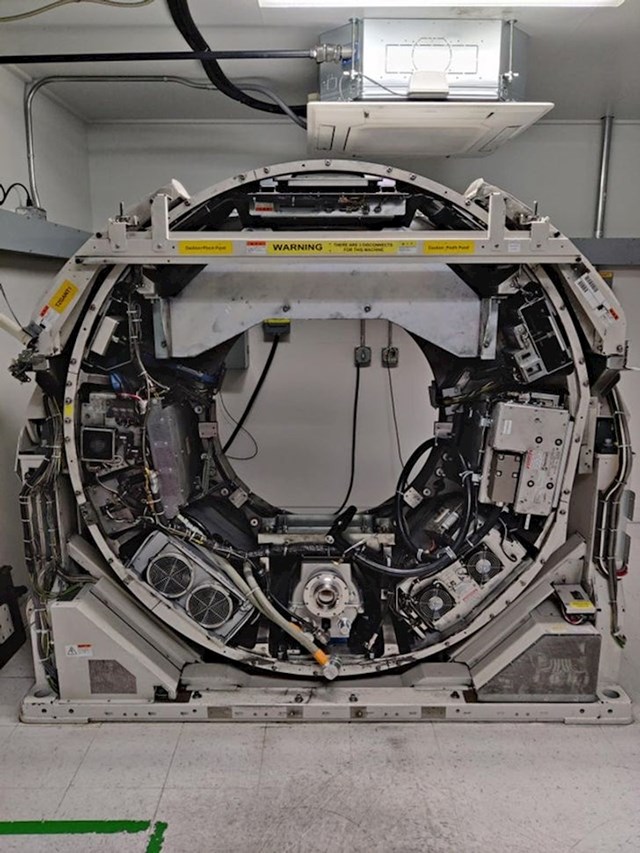

7. Ovako izgleda CT uređaj bez zaštitne plastike